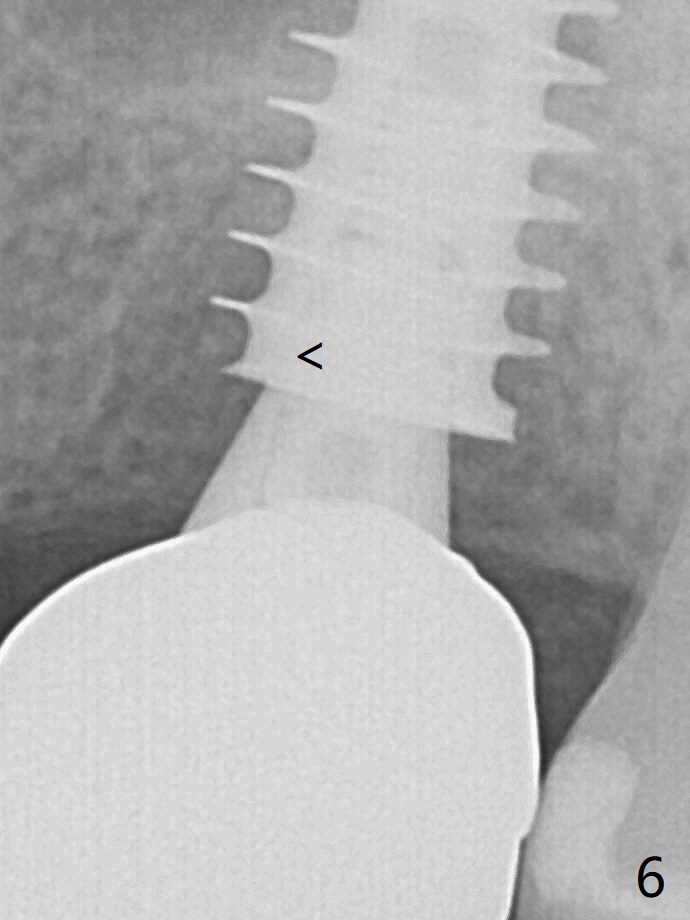

With insertion of Vanilla graft for sinus lift through the buccoapical portion of the osteotomy mentioned above, a 6x11 mm implant is placed with the same trajectory (Fig.2, <40 Ncm). With adjustment of a 6.5x4(3) mm abutment and placement of Vanilla graft in the remaining sockets (Fig.2 *), an immediate provisional is fabricated. The abutment becomes loose again 4 months later. Prior to retightening, a 6 mm profile drill is used. BW shows no bony interference (Fig.5 (opposing tooth occlusal wear; bruxism)), while PA shows the buccal bone, suggesting poor trajectory (guide essential). The gap between the abutment and implant (Fig.6 <) is smaller than that in Fig.3. Thin Septum Last Next Xin Wei, DDS, PhD, MS 1st edition 01/17/2020, last revision 12/19/2020